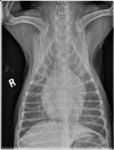

Latérale droite